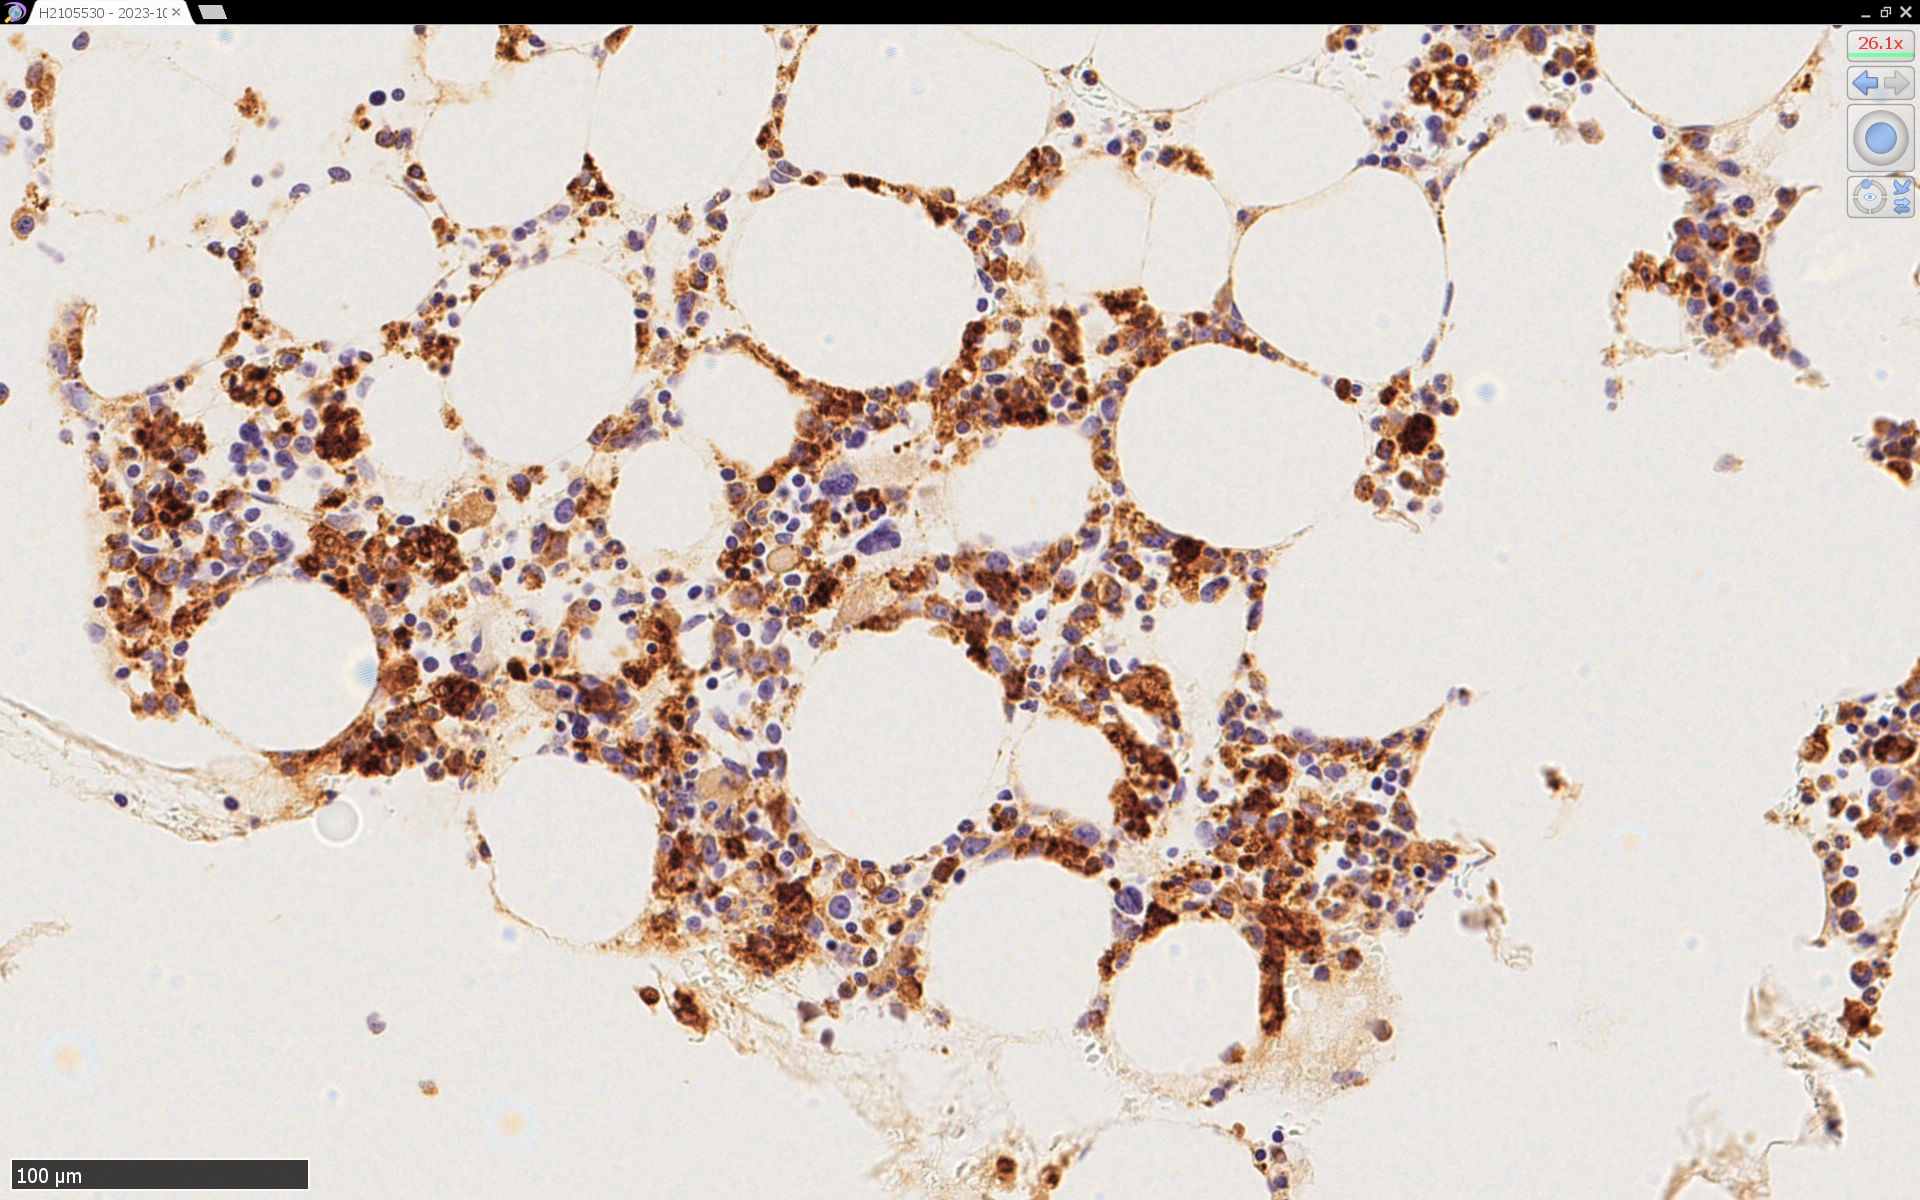

CD68(KP-1)

CD68(PG-M1)